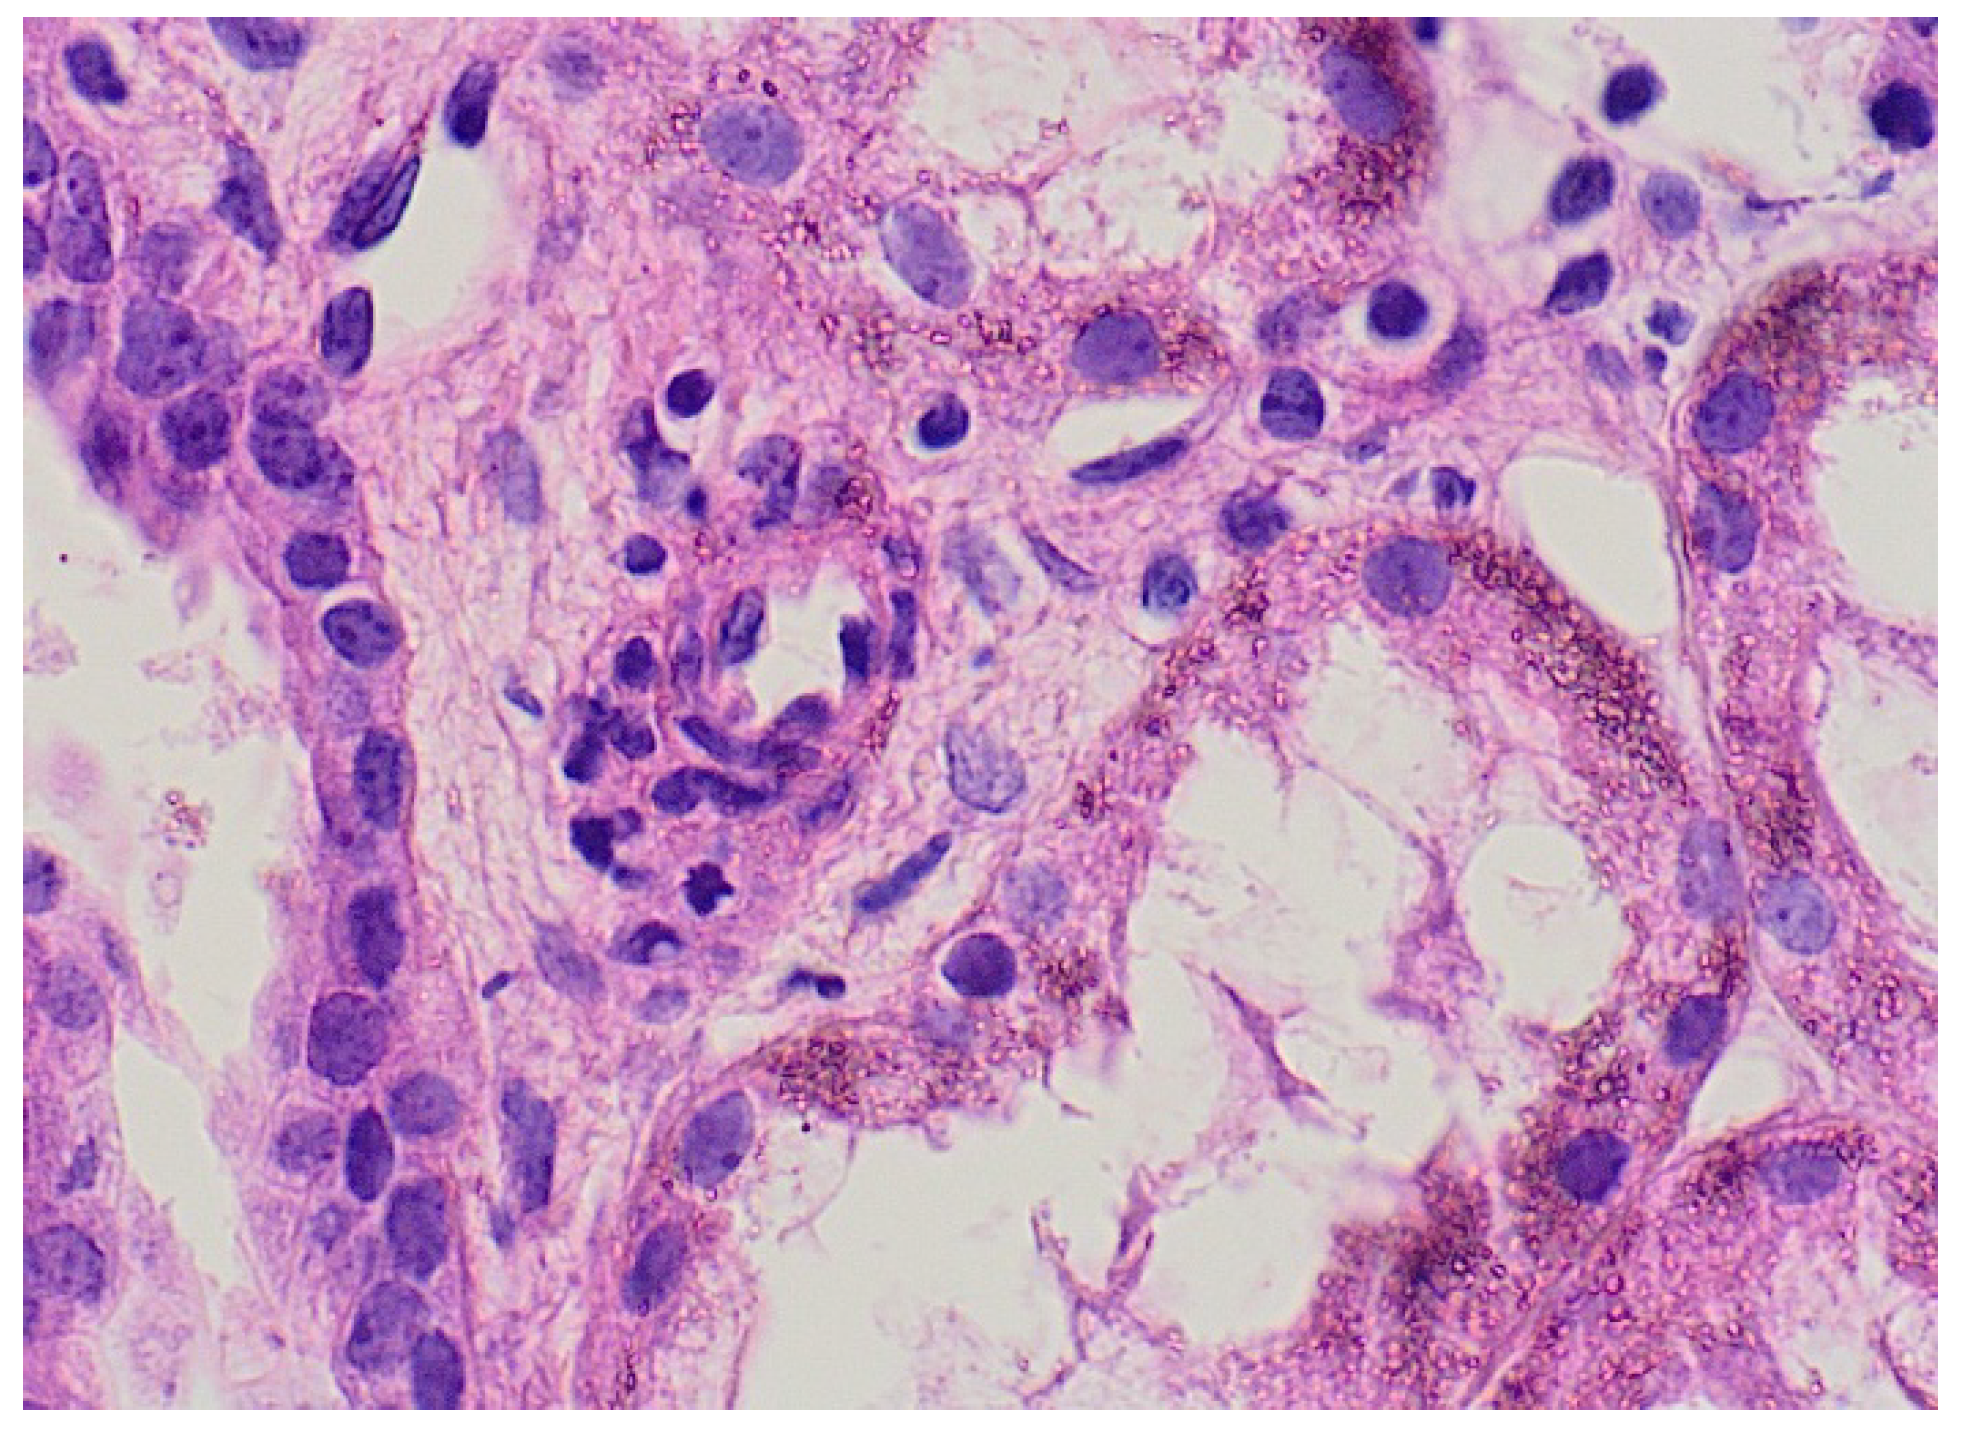

Three cases (14.3%) with renal involvement developed nephritis and required renal biopsy due to persistent hypertension and renal impairment (Figure 4). Proteinuria and WBCs were present in the urine analysis of patients with renal involvement (5/21: 23.8%; Table 2 and Table 3). Leukocytosis was present in 46% (41/89) of all cases and 47.6% of cases with renal involvement. Urinary WBCs were present in 11 patients with renal involvement (11/21; 52.3%).

Figure 4.

Renal biopsy from a 4-year-old boy with IgA vasculitis with renal impairment, the glomeruli showing mesangial proliferation with no crescent formation. (a) Low power and (b) high power.